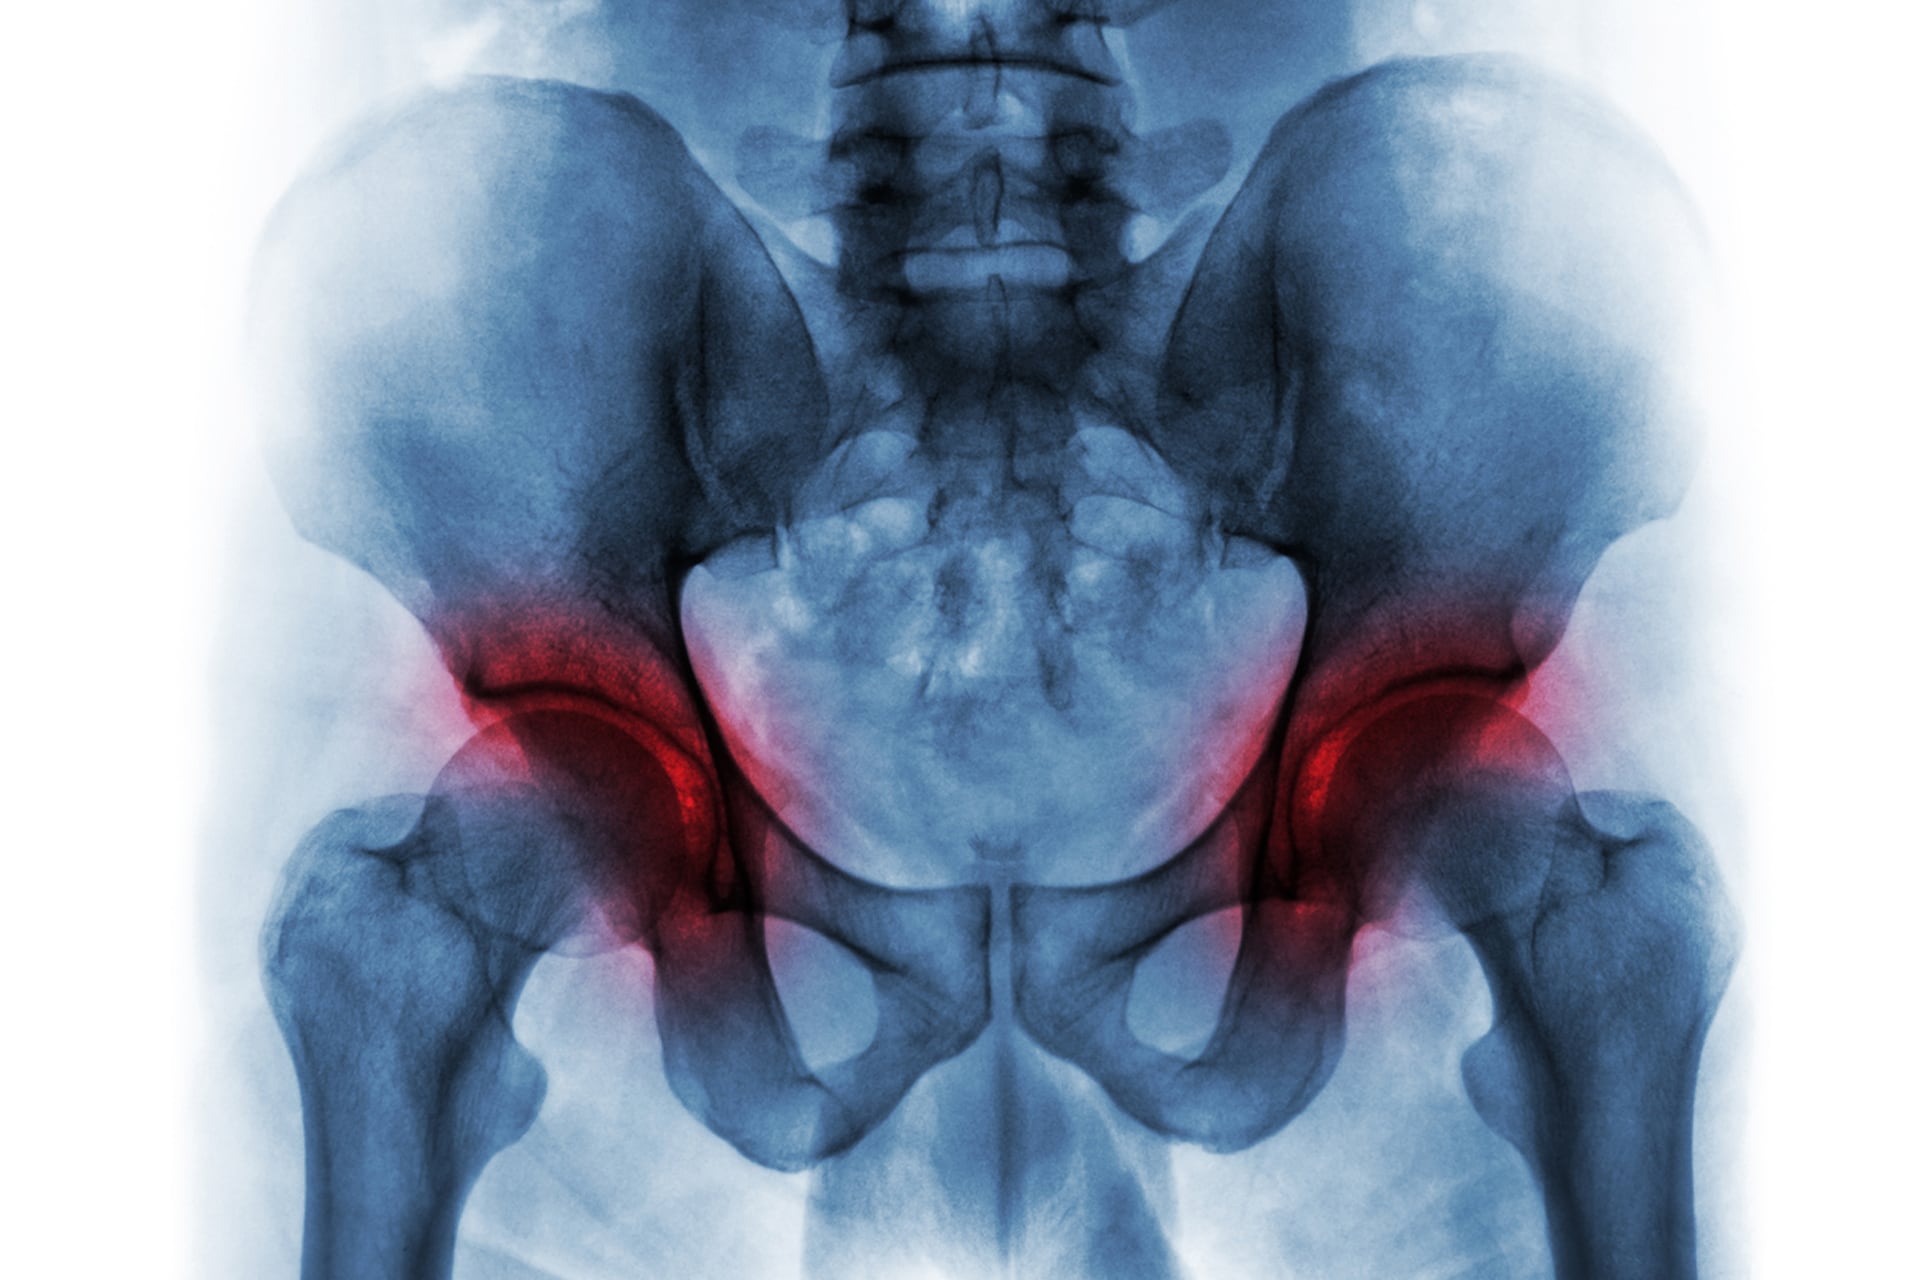

Un estudio en personas mayores encontró que los desequilibrios musculares en piernas, detectados mediante técnicas de imagen, se relacionan con un avance más rápido de la artrosis (Imagen Ilustrativa Infobae)

El estudio, realizado en Asia, involucró a 79 personas mayores de 50 años con dolor reciente en la rodilla y signos de artrosis confirmados por imágenes médicas. Los participantes se sometieron a exámenes que midieron la masa muscular y su distribución en las piernas, utilizando tecnología de última generación.

Según los resultados, la pérdida de masa muscular en ciertas áreas de la pierna, especialmente en la zona externa del muslo, se relacionó con un avance más rápido de la artrosis de rodilla. A su vez, la disminución muscular en la parte interna de la pierna se asoció con un aumento del riesgo de sarcopenia.

De acuerdo con los autores, la masa muscular lateral del muslo y la medial de la tibia tienen un papel relevante en el desarrollo de ambas enfermedades. El desequilibrio entre estos grupos musculares puede acelerar el deterioro articular y favorecer la pérdida de fuerza y masa muscular general.

La investigación utilizó radiografías digitales de cuerpo entero y absorciometría de rayos X de energía dual, técnicas que permiten obtener una imagen detallada de la anatomía muscular. Estos métodos ofrecen datos precisos para cuantificar la masa muscular y su distribución, sin procedimientos invasivos.